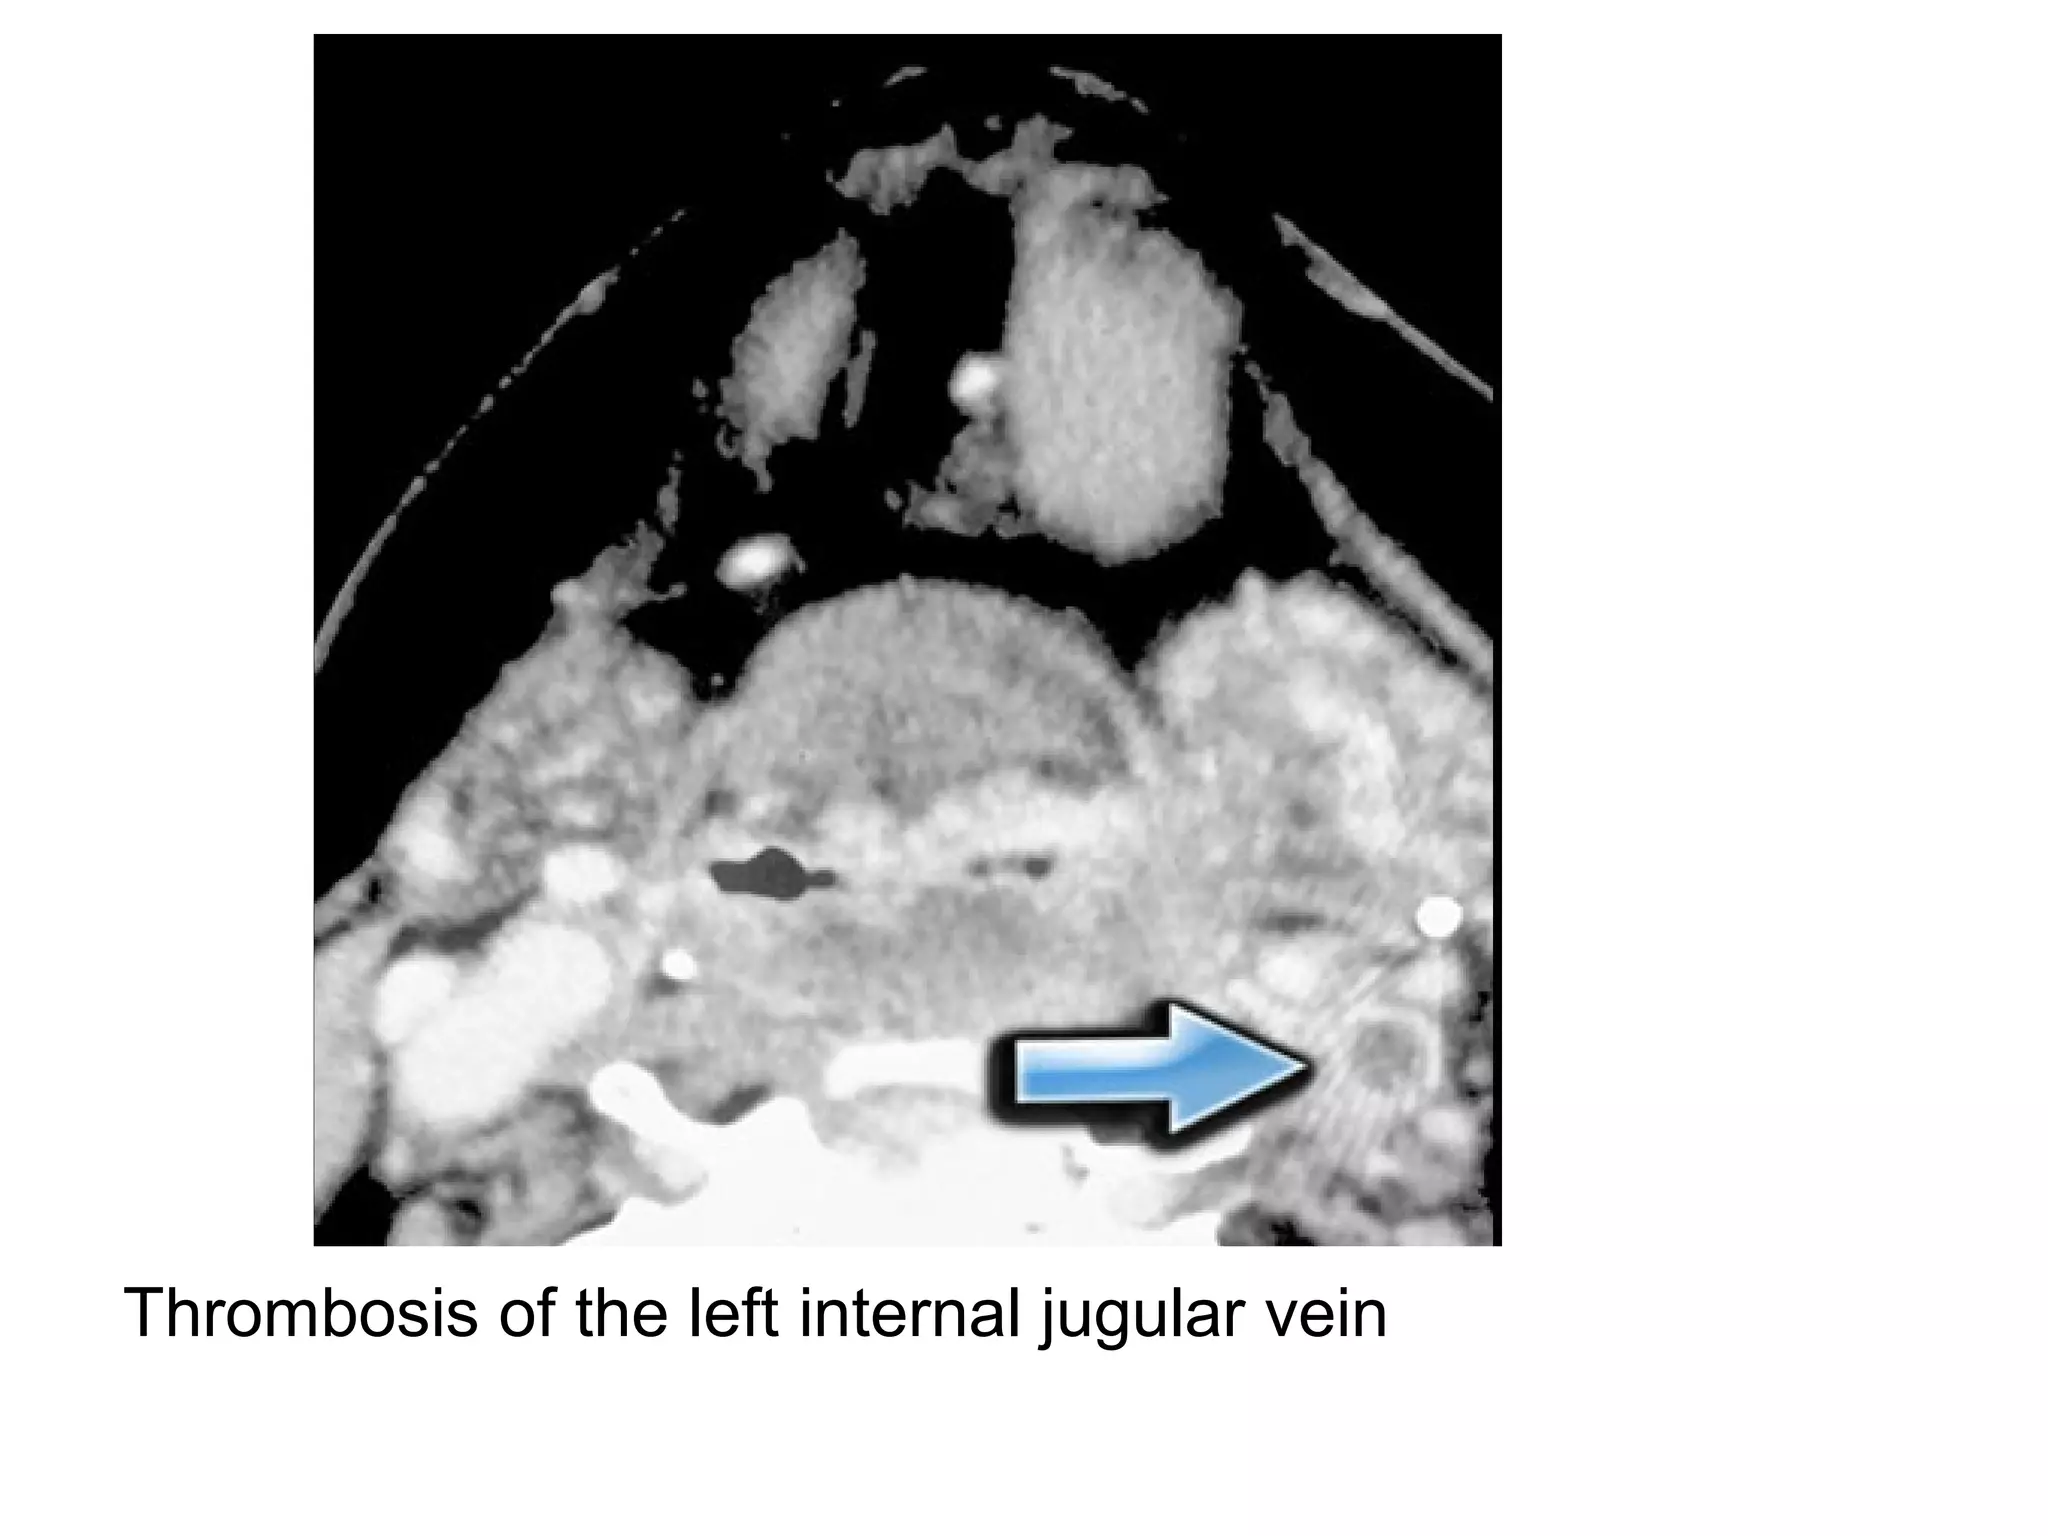

Thrombosis of IJV

Thrombosis of jugular vein

Thrombosis of the left internal jugular vein

Thrombosis of theleft internal jugular vein